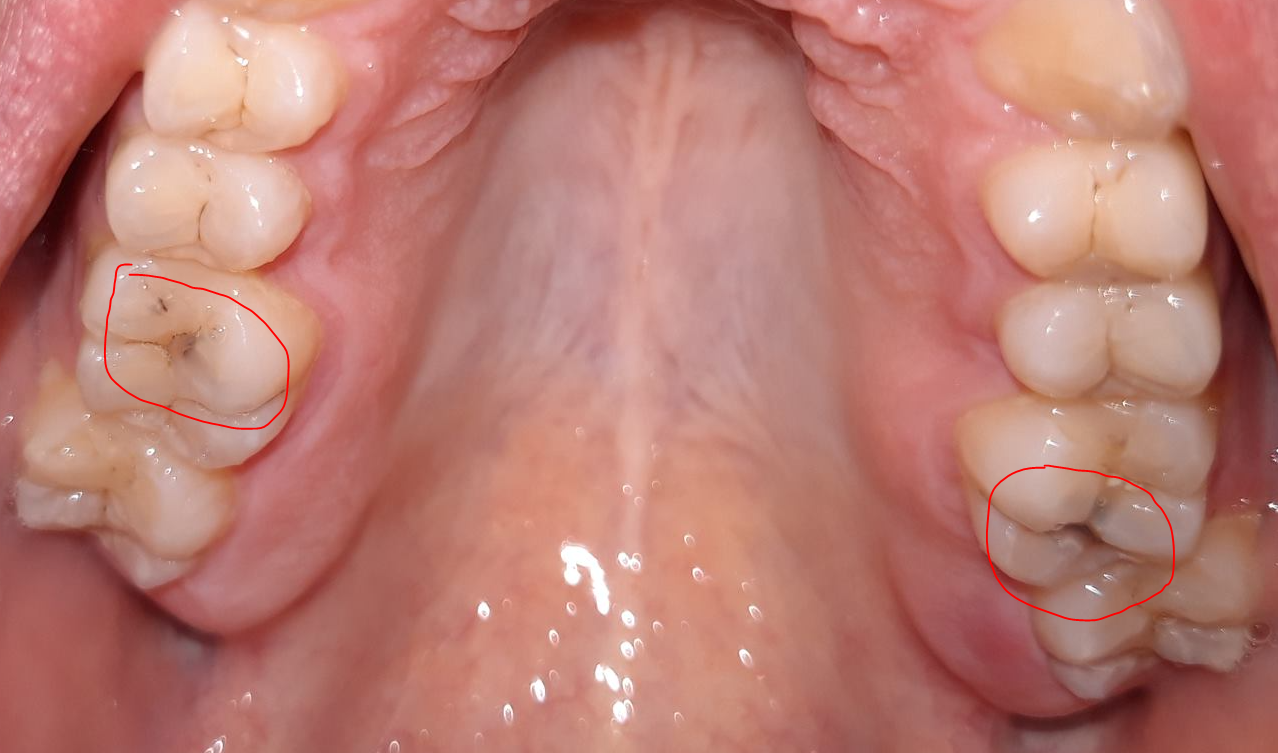

Nu heb ik sinds een aantal dagen wat gevoelig tandvlees op 1 plek en toen ik net keek zag ik wat donkere vlekken op de tand die in de buurt zit.

Nu vraag ik me dus af of die donkere vlekken die een beetje onder het oppervlak liggen van de tand boosdoeners of gaatjes zijn waar ik wat mee moet.

De donkere plekken op uw tanden lijken op beginnende gaatjes. Hoe diep de gaatjes doorgedrongen zijn, zijn niet zo op een foto te beoordelen, maar alleen in de mond door de tandarts. Gaat u vrij regelmatig naar de tandarts? Dan kan het zo zijn dat deze verkleuringen gemonitord worden door de tandarts. Dit betekent dat ze op het moment nog niet dermate erg zijn dat ze gevuld moeten worden, maar in de toekomst mogelijk wel. De donkere plekken zijn niet de oorzaak van de gevoeligheid van het tandvlees.